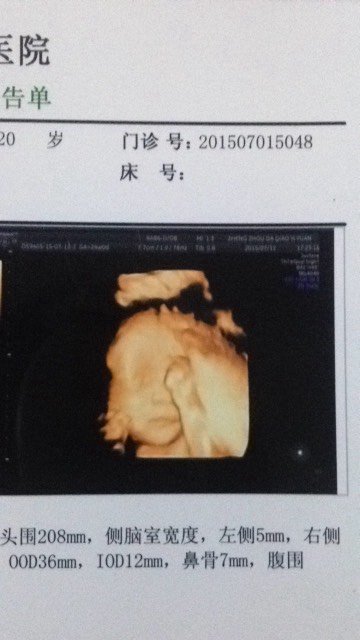

我闺女的四维彩超出来啦,是瓜子脸哦!没有我的娃娃脸不高兴 仿她爹了,她爹还说如果长得像我他就不抱她 我闺女的四维彩超出来啦,是瓜子脸哦!没有我的娃娃脸不高兴。仿她爹了,她爹还说如果长得像我他就不抱她不跟她玩不带她上街说太丢人。😭😭😭 点击展开 厌人心 - 2015-07-13 20:22 为您推荐: 其他回答 祝你好运。 2644391592v号 2015-07-13 20:55 祝宝妈好孕 7喜 2015-07-13 20:54 祝你好孕。。 奇葩女神蹦擦擦。 2015-07-13 20:54 呵呵 挺好的 莪☆╮蘇妲巳祗爲軍而妖 2015-07-13 20:44 哈哈哈。z 你若安好、便是晴天_M54E 2015-07-13 20:40 加载更多 相关问题 26周四维彩超回来,儿子PK爹小时候,看长得像不像!? 这闺女还是和爹亲呀 闺女果然跟爹亲啊…